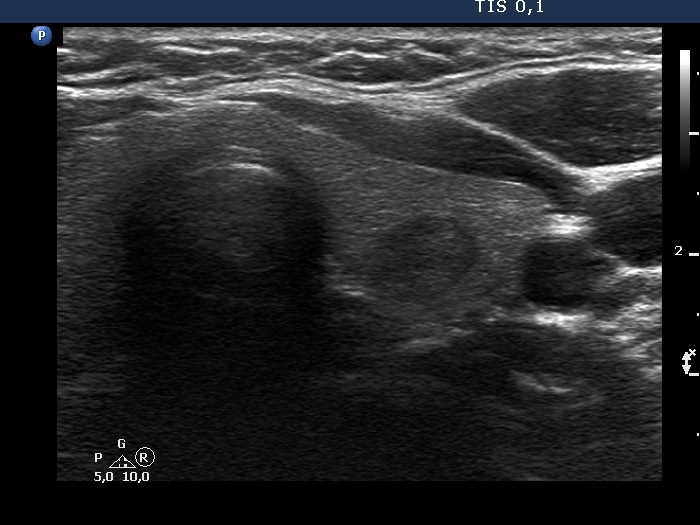

Ultrasonography. The thyroid was echonormal. There was a discrete, deeply hypoechoic area in the dorsal part of the right lobe. Although the dimensions were only 4x7x5 mm, width, depth, length, respectively, the lesion would correspond to a TIRADS 5 lesion because it was very hypoechoic and presented with irregular shape. However, color Doppler mode proved that this was indeed a vessel and not a solid thyroid tissue. The left lobe had a minimally hypoechoic lesion which largest diameter was 9 mm.